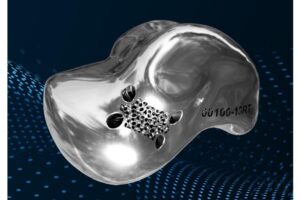

Patient-specific Talus Replacement